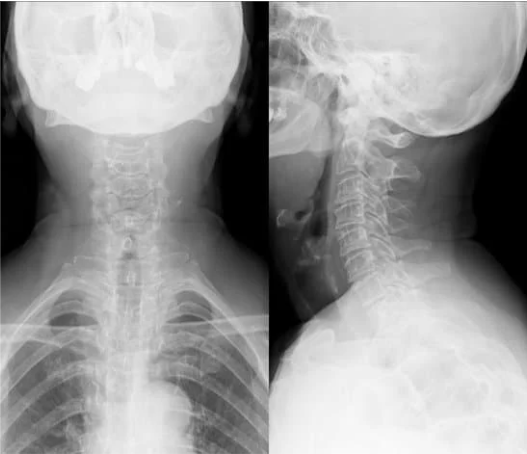

頚椎症の診断はヘルニア同様、痛みしびれの範囲、レントゲン、MRIで行います。レントゲンで骨と骨の隙間が狭くなっていたり、骨がずれているなどの変性所見(加齢性の変化)があると頚椎症を考えます。

頚椎症の診断